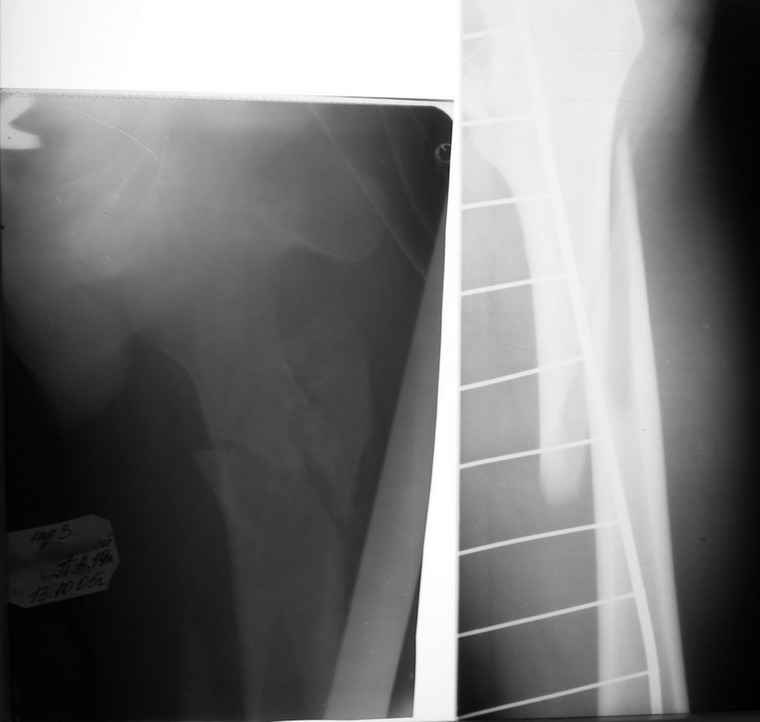

Если снимок справа по хронологии последний, то в тазобедренном сустава наступил анкилоз. Это хороший плюс костной ткани для постановки чашки эндопротеза, но отсутствие сохранения биомеханической оси бедренной кости ставит под вопрос благоприятный вариант усановки ножки эндопротеза.... Учитывая выполненную остеотомию, не считаю выполнение скелетного вытяжения лишенным смысла, для восстановления оси конечности с последующим, возможно, индивидуальным эндопротезированием.

Очень признателен Вам за ответ, но позвольте мне не согласиться с Вами. Я бы пока не делал вывод о анкилозировании тазобедренного сустава. На рентгеновских снимках, да и по данным компьютерной томографии (а этот метод один из самых современных и информативных), хорошо прослеживается постоянной ширины щель между головкой бедренной кости и вертлужной впадины. Кроме того, несложно увидеть разницу "шеечно-диафизарного угла" до и после выполнения тракции в аппарате. Хотя, Алексей, даже если я и прав, это не сильно облегчает нашу задачу.

Вот снимки по свежей ситуации, парень 19 лет, длинный оскольчатый перелом бедра от шейки до в-с/3. давно уже ходит на своих ногах.

Представленные Вами рентгенограммы действительно являются примером качественной фиксации спице-стержневым аппаратом. Они, как ни что другое, многое иллюстрируют.

Кроме того, было бы ошибкой ставить знак равенства между нашим и Вашим пациентами. Они не только не похожи, разница между ними просто огромная. Говорю это не для того, чтобы задеть Вас или обидеть. Ни в коем случае. Просто теперь я понимаю, что Ваше мнением строится на простом преломлении Ваших подходов к лечению пациентов со свежими переломами, на ситуацию, абсолютно несопоставимую, подобную нашей.